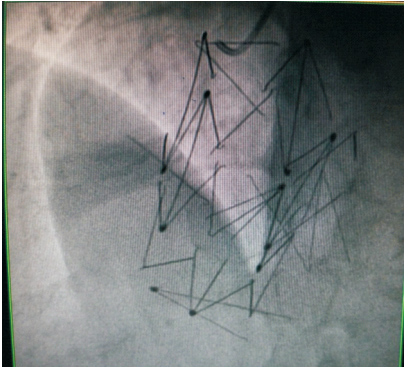

患者59岁,女性,因“发现心脏杂音3个月”于2011年1月份入院。患者2001年因下腔静脉狭窄于外院行下腔静脉支架植入术(支架厂家及型号不详),术后服用培达3个月后停药,无不适。2007年间断出现心悸及胸闷,未诊治。2011年单位体检发现心脏杂音,外院超声提示下腔静脉支架移位至右房,主动脉窦右房瘘。既往:体键。入院查体:血压120/70 mmHg(1 mmHg=0.133 kPa),心律齐,主动脉瓣第一听诊区可闻及Ⅲ/6级收缩期杂音,腹软,无压痛,双下肢不肿。入院诊断:下腔静脉狭窄,下腔静脉支架植入术后,下腔静脉支架移位,主动脉窦右房瘘。入院后相关检查:超声心动图:LV 53 mm,EF 74%,主动脉右冠窦与右房间探及破口约3~4 mm,下腔静脉入右房口处探及支架回声,支架突入右房约20 mm;胸片(图 1、2):侧位片金属支架结构影不连续,心影区偏前区可见线状高密度影。CT(图 3、4):右室游离壁、间隔壁、三尖瓣口、右房、下腔静脉近心段可见支架金属丝影。冠状动脉造影检查(图 5、6):冠状动脉未见明显异常,可见支架影随着心脏的跳动位置发生变化。

患者于2011年2月11日在全麻低温体外循环下行主动脉窦瘤修补+下腔静脉移位支架取出术,术中所见:主动脉右冠窦瘤,主动脉侧直径4 mm,右心房侧破口8 mm,原植入之下腔静脉支架散落,两个分别呈V字形和N字形嵌入右心室腔内,部分突入右心房及嵌入房间隔内,部分游离于或嵌入下腔内。经主动脉切口采用自体心包补片修补窦瘤破口,切开右心房取出散乱的支架以及右心室残留的支架,术中拍片(图 7)复查仍有部分支架残端位于远离心脏的身体其他部位,无法取出。术后复查超声:LV 44 mm,EF 62%,主动脉窦瘤消失,窦壁修补完整。复查CT(图 8):左肺下叶外侧基底段(1根,长约20 mm)、右心房室内、下腔静脉仍有细线状高密度影(2根,长度分别为21 mm、19 mm)。